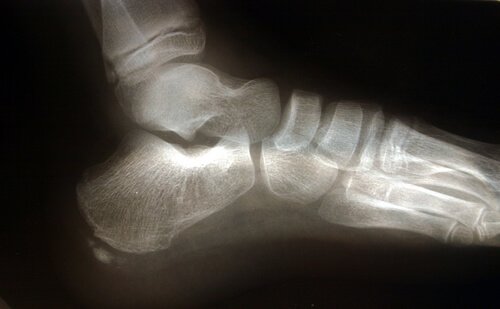

Fodens anatomi

Der er flere anatomiske strukturer, som spiller en rolle i enhver overbelastning af plantar fascia.

Akillessenen er en sene, som forbinder gastrocnemius musklerne, bedre kendt som lægmusklerne, og soleus musklerne med hælen. En sammentrækning af akillessenen udløser en øgning af presset på hælen, med den resulterende øgning af tryk på plantar fascia.

En anden faktor at have i baghovedet omkring den anatomiske struktur er fodens strækning, eller med andre ord, hvordan foden rammer jorden. Flade fødder eller fødder med tendens til at overpronere strækker plantar fascia mere, dermed øger det risikoen for brud på grund af det ekstra tryk på vævet.

Plantar fasciitis er ofte forbundet med tilstedeværelsen af knoglespore, selvom det ikke er en afgørende faktor.